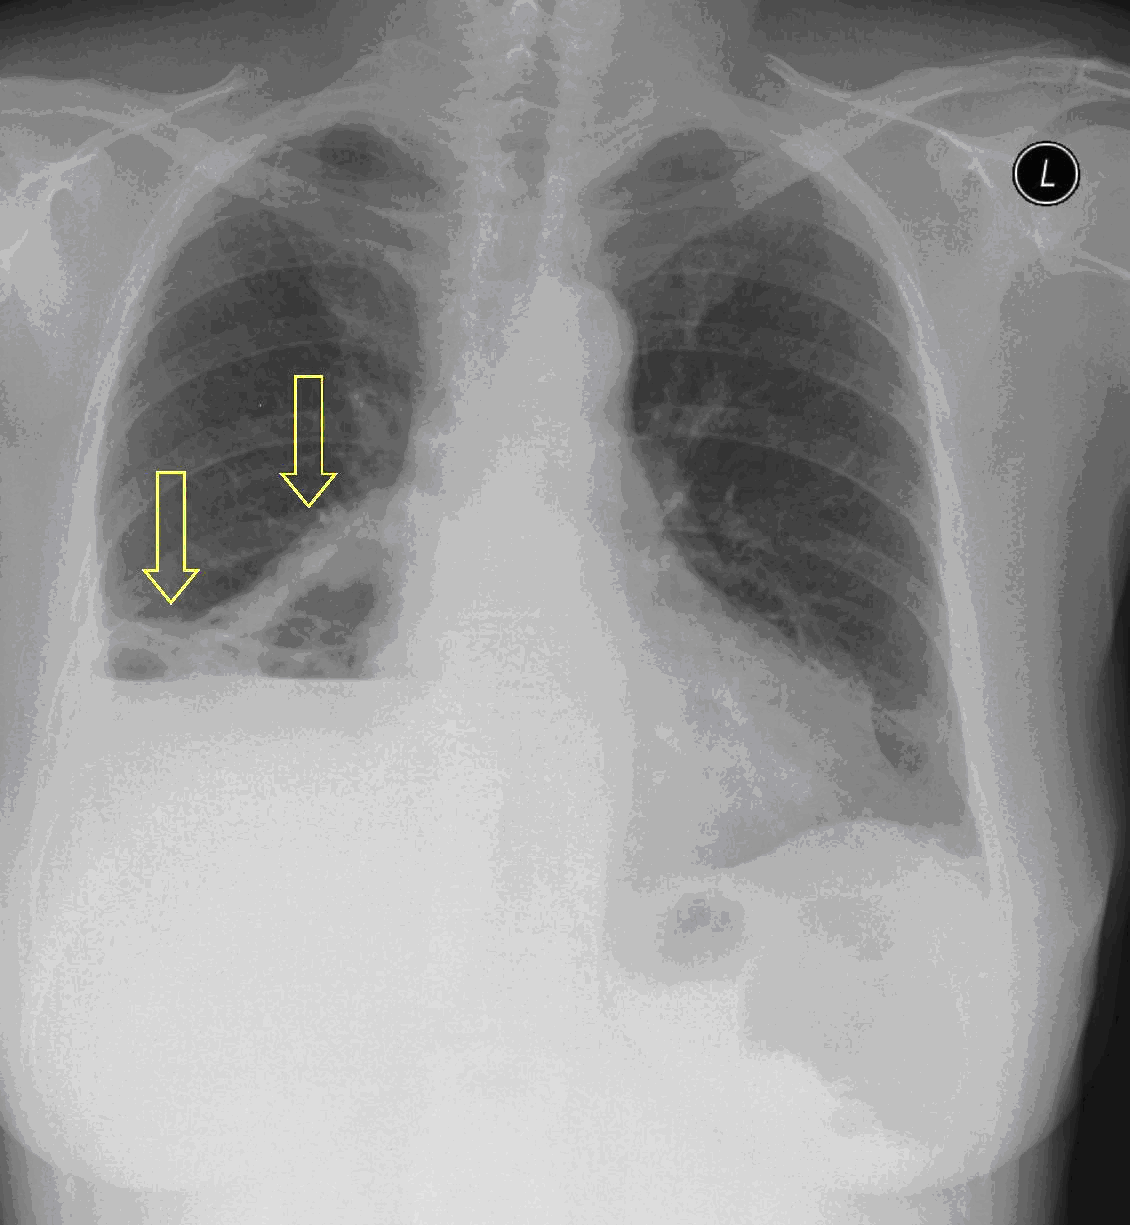

3a: Round shadow: multiple lung metastasis. Chest radiograph (PA)

3b: Multiple lung metastasis, CT lung window (axial, coronal reformat)

3c, coronal reformat

70 year old man, colon tumor.

Radiograph: Bilateral extensive, confluating patchy-nodular shadowing with diffuse reticular pattern. The diaphragm contour is partially blurry bilaterally: lymphangiosis carcinomatosa.

CT: Numerous 1-6 cm round and irregular, lobulated-spiculated contrast enhancing lesions in both lungs, everywhere sporadically.